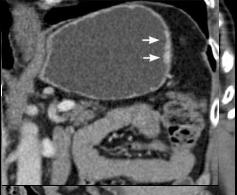

Adeno carcinoma

de l'estoma , forme linite plastica avec

epaississement maruee de la paroi gastriue ( image

TDM en coupe axiale |

Meme cas en coupe coronale (frontale

) |